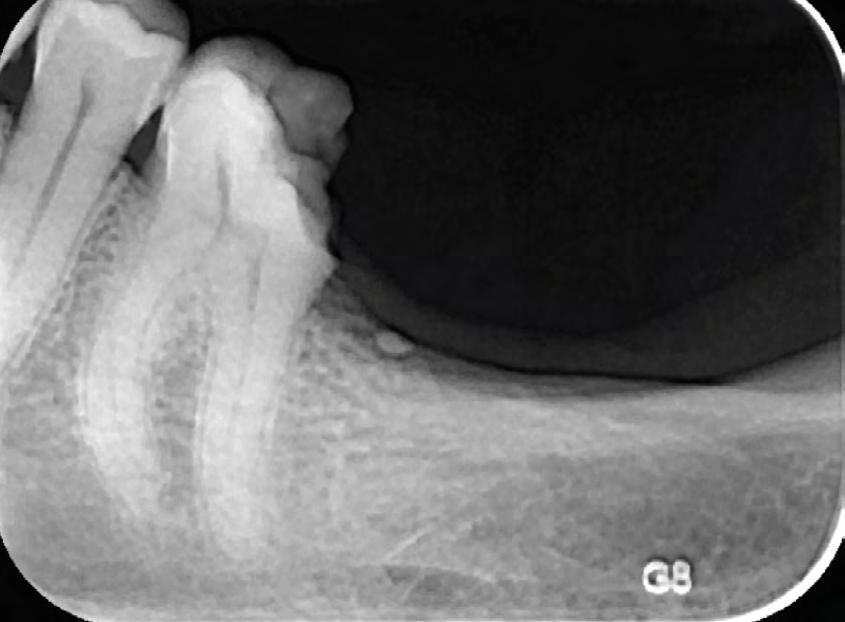

This case was referred to me by a doctor who was unable to negotiate his patient’s tortuous, ledged, and calcified canals, possibly because he did not have the ideal instruments for the case. During treatment, I negotiated the patient’s canals to apex using my #8 and #10 files. From there, I used EdgeGlidePath by EdgeEndo, which performs ideally in tight canals. When it began to bind after 1–2 mm, I paused to irrigate the area, recapitulated with my #10 file, and reentered with the EdgeGlidePath file to length.

Thanks to the flexibility and ease of use offered by EdgeOne Fire files, I completed this root canal rapidly and safely. Preop and postop images taken 4 months apart display signs of successful healing and an absence of a fistula. I think these files are great tools that every clinician should have.

Preop vs. Postop Radiographs taken 4 months apart